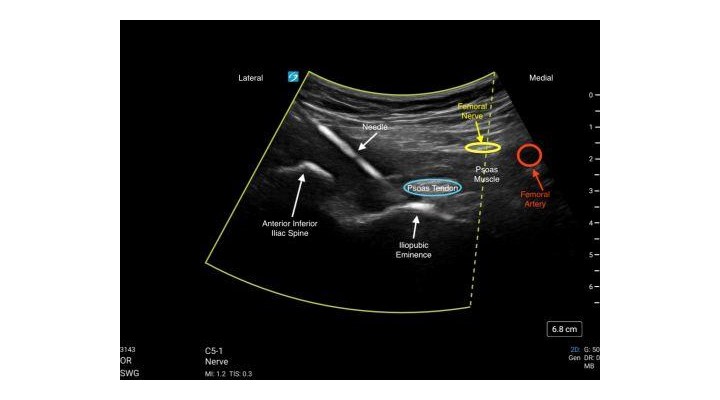

- Slide the transducer inferiorly, maintaining visualization of the pelvis to identify the Anterior Inferior Iliac Spine, the Iliopubic Eminence, the Psoas Tendon and Femoral Artery.

- Use the in-plane needle technique with a lateral to medial approach to target the injection of local anesthetic deep to the Psoas Tendon.

C5-1 Curvilinear